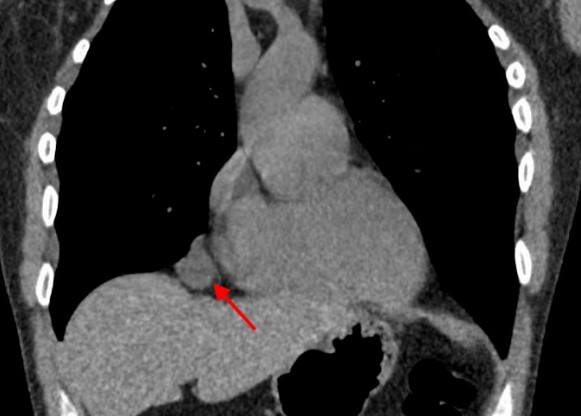

Рентгеновские снимки тератомы средостения: Диагностика и лечение